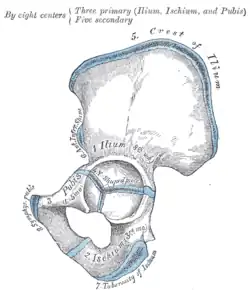

Darstellung der Ossifikation eines Hüftbeines -

Hüftbein (Os coxae)

Beide Hüftbeine bestehen aus je drei Anteilen:

Diese drei Knochen verschmelzen beim Menschen etwa mit dem 15. Lebensjahr im Bereich der Hüftgelenkpfanne zum nun einheitlichen Hüftbein.